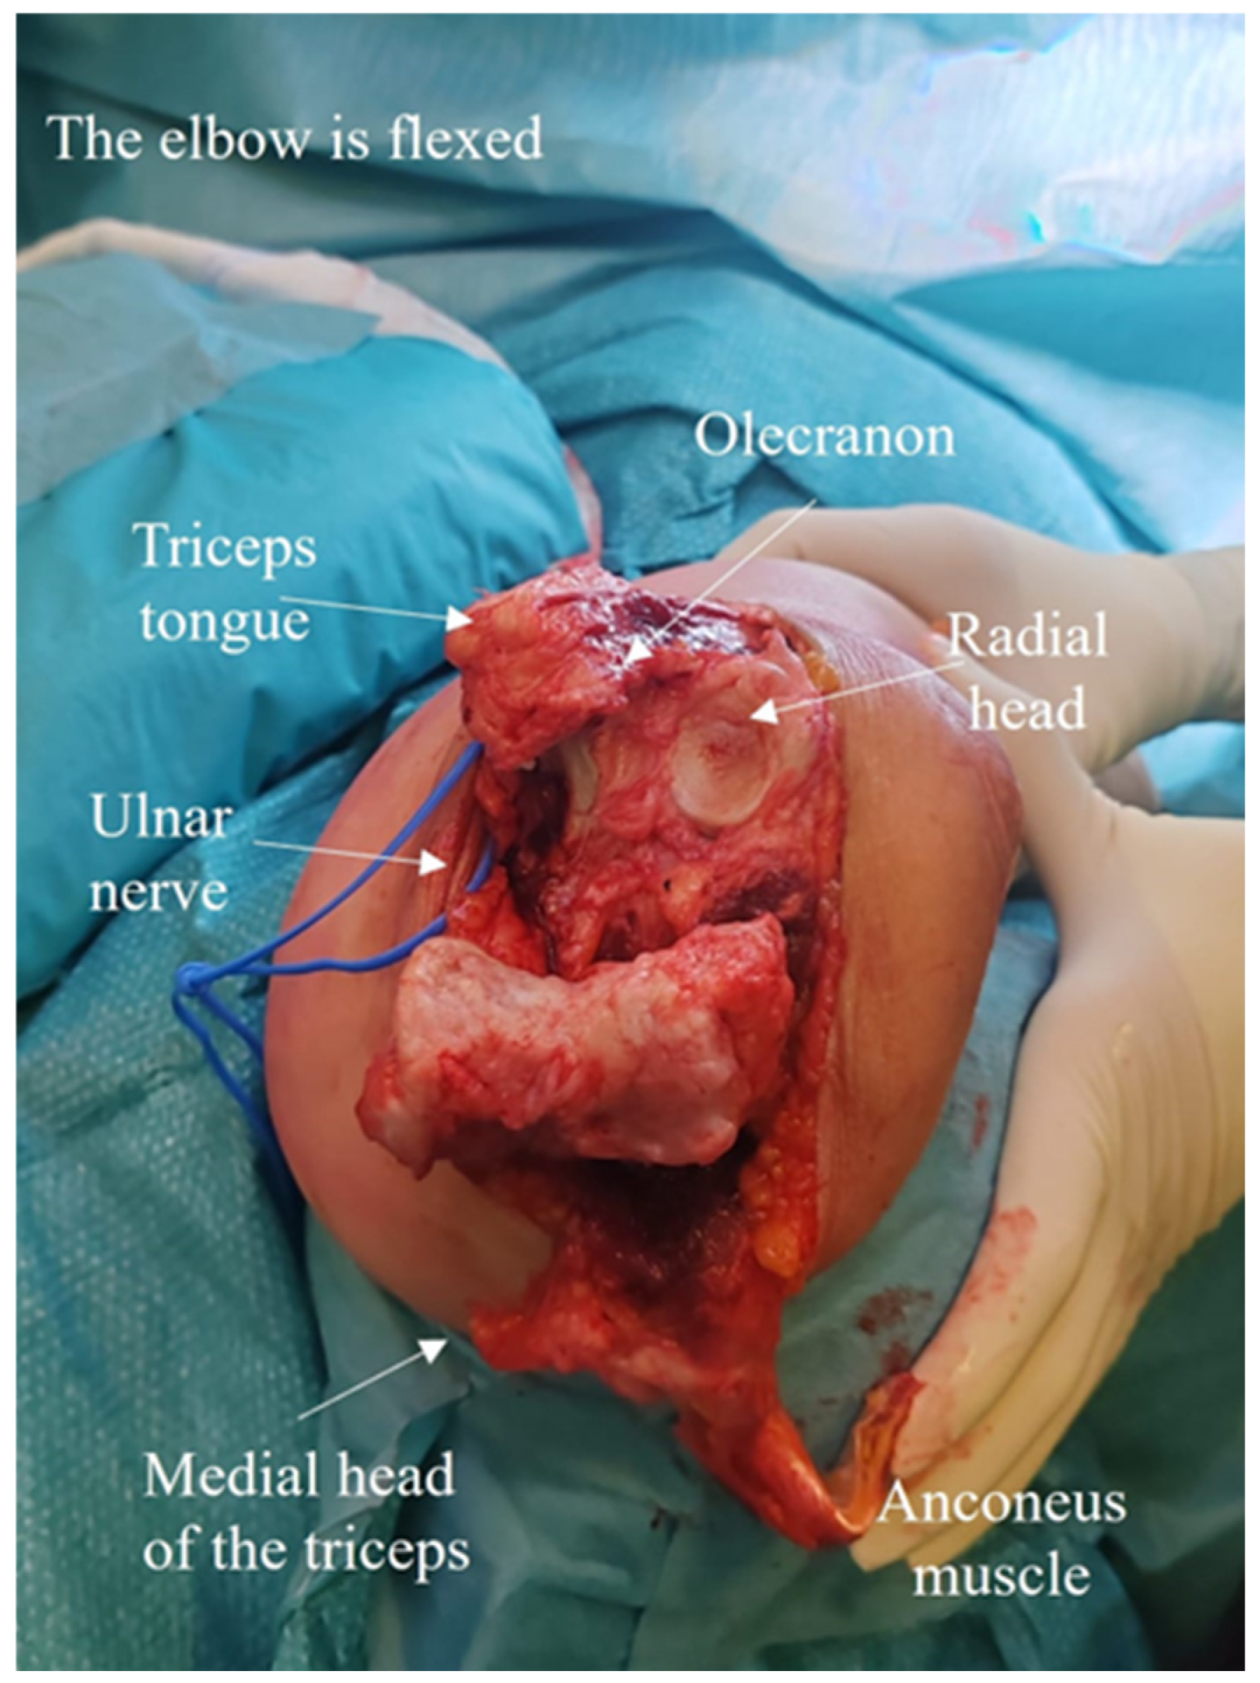

2.4. Development of the ARTT Approach